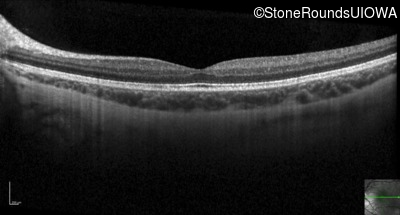

Optical Coherence Tomography - Right - 20/25 -2

Exemplar / OCT Stack